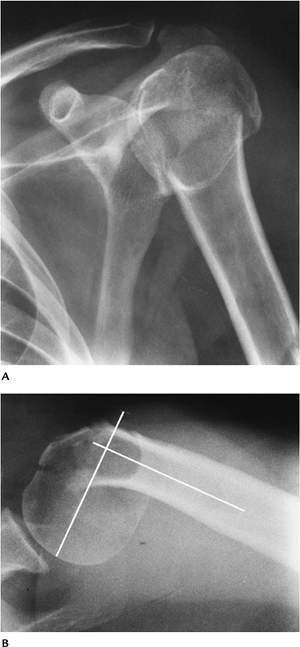

FIGURE 7-2 AP (A) and axillary (B) views of a comminuted impacted proximal humeral fracture. The fracture is angulated (lines) greater than 45 degrees.

FIGURE 7-3 Four-part fracture with marked displacement of the fragments. The patient was treated with a shoulder prosthesis. AP (A) and axillary (B) views.